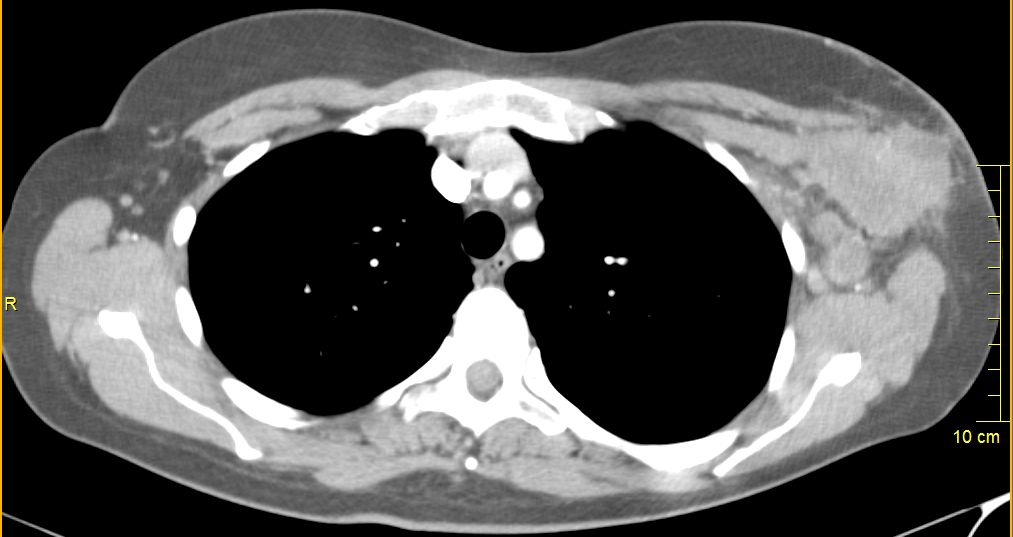

mediastinale Lymphknoten

75-jährige Frau mit triple-negativem Mammakarzinom. Chemotherapie abgelehnt. Im Planungs-CT Lymphknotenvergrößerung mediastinal und parasternal.